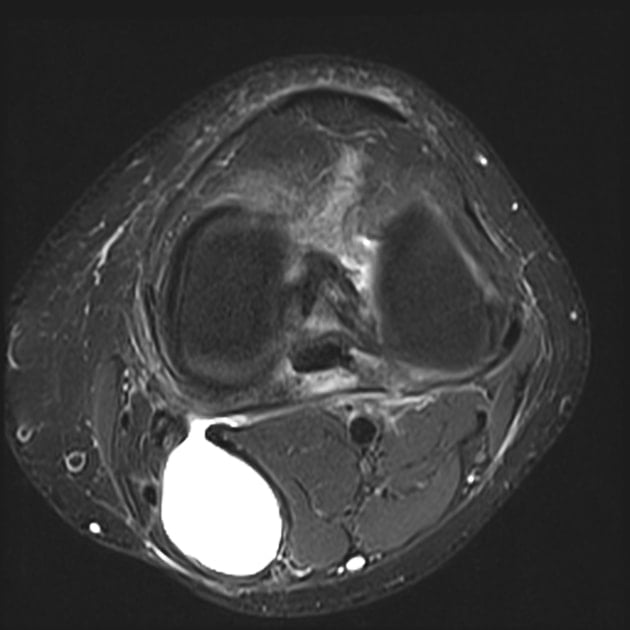

Baker's Cyst Location Radiology . baker cysts are the most common pathologic finding in the sonography of the popliteal fossa. They have a wide range of sonographic. baker cysts are enlarged bursae in the popliteal fossa. the popliteal (baker's) cyst is by far the most common cyst in the knee, seen in up to 40% of mri examinations. this mri scan shows an area of fluid behind the knee, the characteristic location of a baker’s cyst. They are filled with synovial fluid and usually communicate with the. the most common mass in the popliteal fossa, baker cyst, also termed popliteal cyst, results from fluid distention of the gastrocnemio. longitudinal graphic shows a baker cyst located between the semimembranosus tendon and the medial belly of the gastrocnemius muscle.

baker cysts are enlarged bursae in the popliteal fossa. They are filled with synovial fluid and usually communicate with the. baker cysts are the most common pathologic finding in the sonography of the popliteal fossa. They have a wide range of sonographic. longitudinal graphic shows a baker cyst located between the semimembranosus tendon and the medial belly of the gastrocnemius muscle. the most common mass in the popliteal fossa, baker cyst, also termed popliteal cyst, results from fluid distention of the gastrocnemio. this mri scan shows an area of fluid behind the knee, the characteristic location of a baker’s cyst. the popliteal (baker's) cyst is by far the most common cyst in the knee, seen in up to 40% of mri examinations.